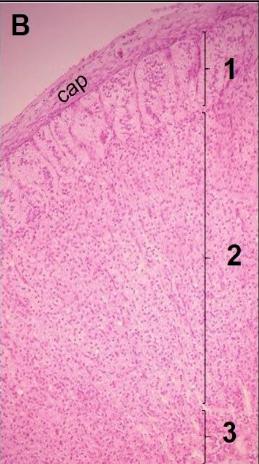

B: Corteza adrenal.

cap: cápsula

1: zona glomerular

2: zona fasciculada

3: zona reticular